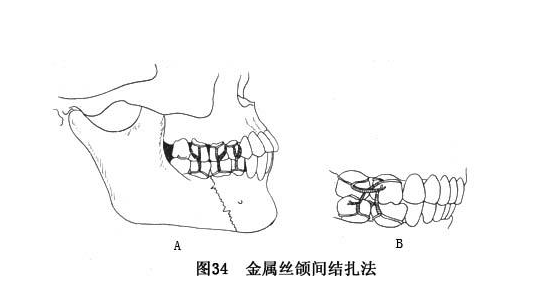

2. 固定的方法:(1)单颌固定 即在发生骨折的下颌骨上进行牙间或骨间固定,适用于无明显移位的线形骨折。目前最常用的固定的方法为单颌牙弓夹板固定。 (2)颌间固定(牵引) 颌间固定是在上下颌牙弓上结扎牙弓夹板,然后用橡皮圈将上下颌骨固定在一起,利用上颌完好的牙弓为依据,以恢复咬合关系,从而恢复下颌骨的连续性。